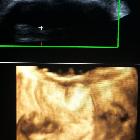

Harlequin

ichthyosis - Prenatal diagnosis with two- and three-dimensional ultrasound at 30 weeks. Three-dimensional sonogram of fetal face shows persistently open mouth with thick lips, flat nose and bilateral orbital swellings.

ichthyosis - Prenatal diagnosis with two- and three-dimensional ultrasound at 30 weeks. Three-dimensional sonogram of fetal face shows bilateral orbital swellings, flat nose, thick lips with rounding of angle of mouth and flat rudimentary ear.

ichthyosis - Prenatal diagnosis with two- and three-dimensional ultrasound at 30 weeks. Three-dimensional sonogram of fetal face shows bilateral orbital swellings.